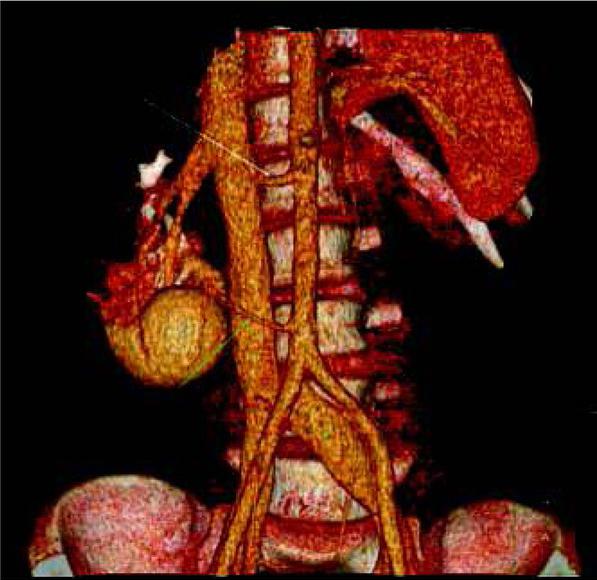

Our analysis showed that one-phase split-bolus LD-CTU protocol is a very effective and dose sparing technique in diagnosis of CAKUT in children. Additionally, it can be adapted to the standard indications agreed by the ESPR and ESUR groups [1, 2]. In renal trauma, not only renal parenchyma can be assessed during one scan, but also vessels and collecting system (fig. 4) [1, 2, 7]. This will reduce the need of multiple scanning, especially that initially the site of injury may be not known. In imaging diagnosis of tumors and complicated infections, parenchymal phase is considered suffcient in most cases [1, 2]. However, in some specific situations additional scans can be required. The primary role of imaging in renal tumors in children is the preoperative assessment and evaluation for metastatic disease [16], including venous invasion. During diagnosis of complicated pyelonephritis, the site of obstruction or congenital abnormality which predisposes to infection [5] can be revealed with one-phase split bolus technique.

Volume reconstruction of CT performed in a 14-year-old boy with agenesis of the left kidney, after traumatic injury of the right kidney. One-phase split-bolus CT shows two renal arteries (arrows) with amputation of the upper artery (white arrow) and no enhancement of corresponding upper and middle part of the kidney. There were no signs of injury of the collecting system.

Ryc. 4. Rekonstrukcja objętościowa TK wykonanej u 14-letniego chłopca z agenezją nerki lewej, po urazie nerki prawej. Jednofazowa TK z podzielonym bolusem środka kontrastowego wykazała obecność dwóch tętnic nerkowych (strzałki) oraz brak zakontrastowania dystalnego odcinka górnej tętnicy (biała strzałka) i odpowiadającej jej środkowej i górnej części miąższu nerki. Badanie nie wykazało zmian urazowych układu zbiorczego nerki.